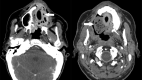

Fig 1.

A and B, A 32-year-old woman status post partial palatectomy for mucoepidermoid Ca and placement of a Trusoft obturator at the palatal defect (black arrow). The obturator bulb (white arrow) is seen extending to the level of the left choana. The bulb is the part of the obturator that inserts into the palatal defect. The postcontrast CT image shows the rounded hyperattenuated appearance of this obturator bulb, which was mistaken for enhancing tumor recurrence.